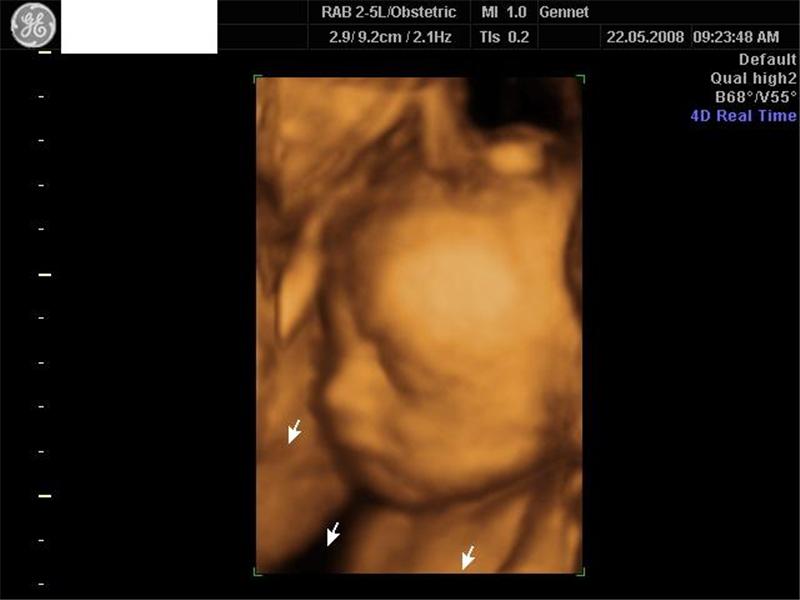

4D ultrazvuk našich dráčků